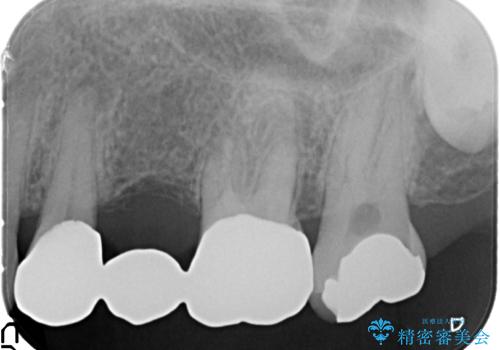

- 20年前に治療した銀歯が壊れ、審美的な修復を希望され来院されました。

銀歯・虫歯を除去し、ジルコニアを咬合再構成を行います。